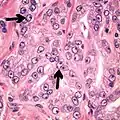

- Multiple nucleoli

- Eccentric nucleoli[4]

-

Acinar adenocarcinoma with multiple nucleoli.